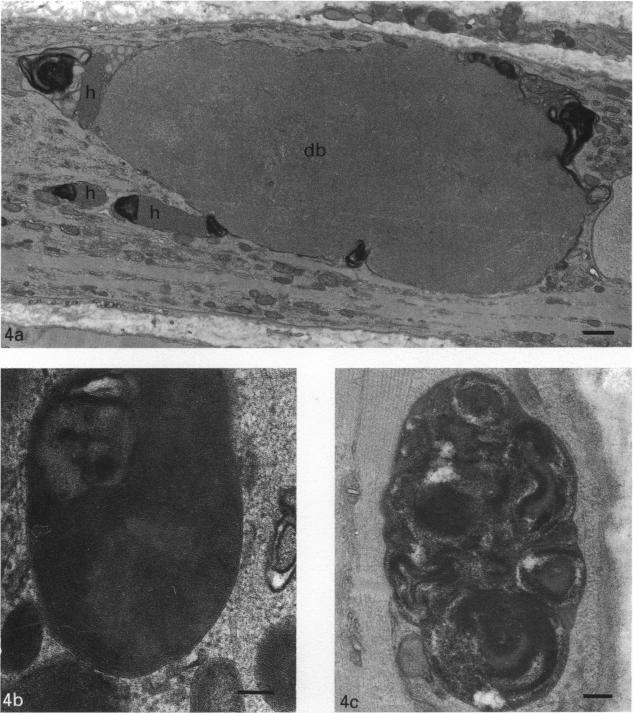

Vitamin E deficiency in rats gives rise to a neuromuscular syndrome that includes a peripheral neuropathy as well as generalised muscle wasting and weakness. This is probably related to damage by oxygen-derived free radicals. In the present study, histological examination of lower limb muscles showed widespread myopathic changes which included the presence of amorphous electron-dense inclusions and tubular aggregates in muscle fibres and muscle fibre necrosis. Histochemical observations suggested a reduction in the activity of oxidative enzymes. The mitochondria showed nonspecific degenerative changes on electron microscopy; no paracrystalline inclusions were observed. Polarographic analysis of isolated muscle mitochondria revealed statistically significant decreases in oxygen utilisation rates with both NADH and FADH2-linked substrates. In confirmation of a generalised respiratory chain abnormality, enzymatic analyses revealed decreases in the activities of complexes I, II/III and IV, although only the decreases in complexes I and IV activities were statistically significant. Measurements of membrane fluidity showed that this is reduced in mitochondria from vitamin E deficient rats, indicating reduced stability of their membranes. The respiratory control ratio, derived from the polarographic results, was also reduced in mitochondria from vitamin E deficient animals, suggesting membrane damage. An altered lipid environment, possibly secondary to a higher level of lipid peroxidation, could result in the inhibition of complexes I and IV. This could also be caused by oxidative damage to the complexes or to mitochondrial DNA. The preservation of citrate synthase activity is against any generalised defect of mitochondrial function. The question as to whether these defects of mitochondrial respiratory chain function are responsible for the muscle fibre damage and necrosis requires further investigation.

大鼠维生素E缺乏会引发一种神经肌肉综合征,包括周围神经病变以及全身性肌肉萎缩和无力。这可能与氧衍生自由基的损伤有关。在本研究中,对下肢肌肉的组织学检查显示广泛的肌病性改变,包括肌纤维中存在无定形电子致密包涵体和管状聚集物以及肌纤维坏死。组织化学观察表明氧化酶活性降低。线粒体在电子显微镜下显示非特异性退行性改变;未观察到副结晶包涵体。对分离的肌肉线粒体进行极谱分析发现,使用NADH和FADH2连接底物时氧利用率有统计学意义的降低。为证实存在全身性呼吸链异常,酶分析显示复合物I、II/III和IV的活性降低,尽管只有复合物I和IV活性的降低具有统计学意义。膜流动性测量表明,维生素E缺乏大鼠的线粒体膜流动性降低,表明其膜稳定性降低。根据极谱结果得出的呼吸控制率在维生素E缺乏动物的线粒体中也降低,提示膜损伤。脂质环境改变,可能继发于较高水平的脂质过氧化,可能导致复合物I和IV受到抑制。这也可能是由于复合物或线粒体DNA的氧化损伤所致。柠檬酸合酶活性的保留排除了线粒体功能存在任何全身性缺陷的可能性。线粒体呼吸链功能的这些缺陷是否是肌纤维损伤和坏死的原因,这一问题尚需进一步研究。